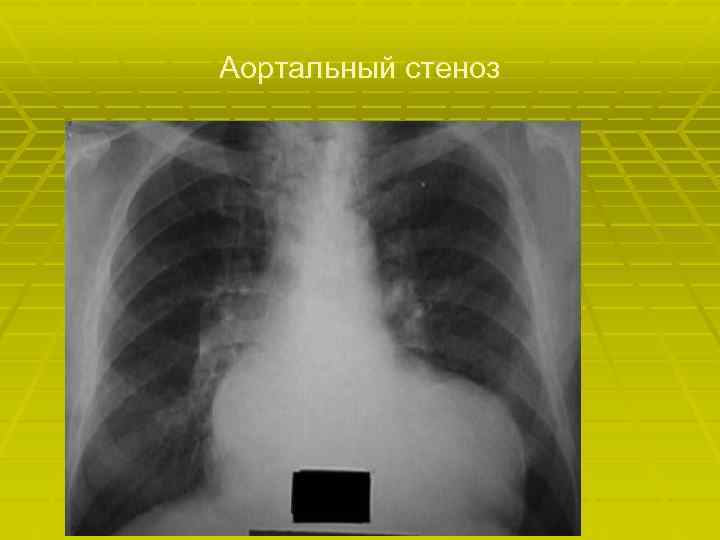

Аортальный стеноз